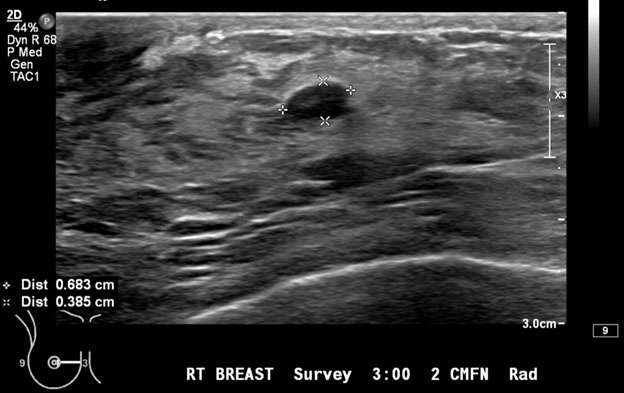

Figure 1: Targeted ultrasound examination of the right breast demonstrated an oval mass with circumscribed margins measuring 7 x 4 x 7 mm seen at 3 o'clock located 2 centimeters from the nipple. Oval mass is probably benign, sonographic follow-up in 6 months is recommended. BI-RADS Category 3: Probably Benign Finding.